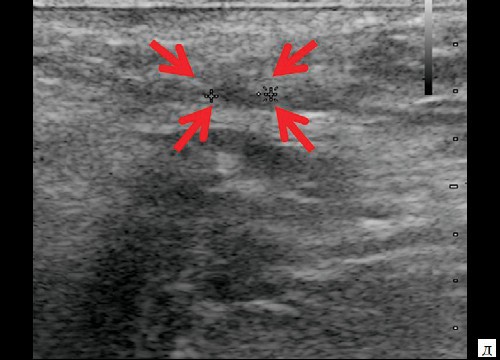

При контрольном УЗ-исследовании через 14 дней после оперативного вмешательства: описываемое гипоэхогенное жидкостное образование с четкими неровными контурами уменьшилось в размере до 1,1×0,6×0,8 см и объеме до 0,29 мл (рис. 3, а, б). Сосудистая реакция в подкожно-жировой клетчатке не определяется (рис. 3, в). Свищевой ход визуализируется нечетко, уменьшился в размере до 0,8×0,2×0,4 см (рис. 3, г).

Рис. 3. а, б – В-режим. Через 14 дней после оперативного вмешательства. Гипоэхогенное жидкостное образование с четкими неровными контурами в перианальной области уменьшилось в размерах до 1,1×0,6×0,8 см, объемом 0,29 мл (стрелки);

в – режим ЦДК. Через 14 дней после оперативного вмешательства. Сосудистая реакция в подкожно-жировой клетчатке не определяется;

г, д – В-режим. Через 14 дней после оперативного вмешательства. Свищевой ход визуализируется нечетко, уменьшился в размере до 0,8×0,2×0,4 см (стрелки).